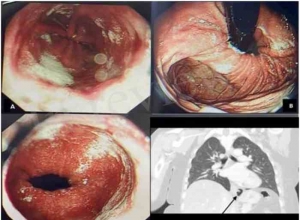

腹腔镜与内镜联合手术治疗胃黏膜下肿瘤的可行性(附视频)Feasibility of laparoscopic and endoscopic cooperative surgery for gastric submucosal tumors (with video)AbstractBACKGROUND AND AIMS:Laparoscopic ...